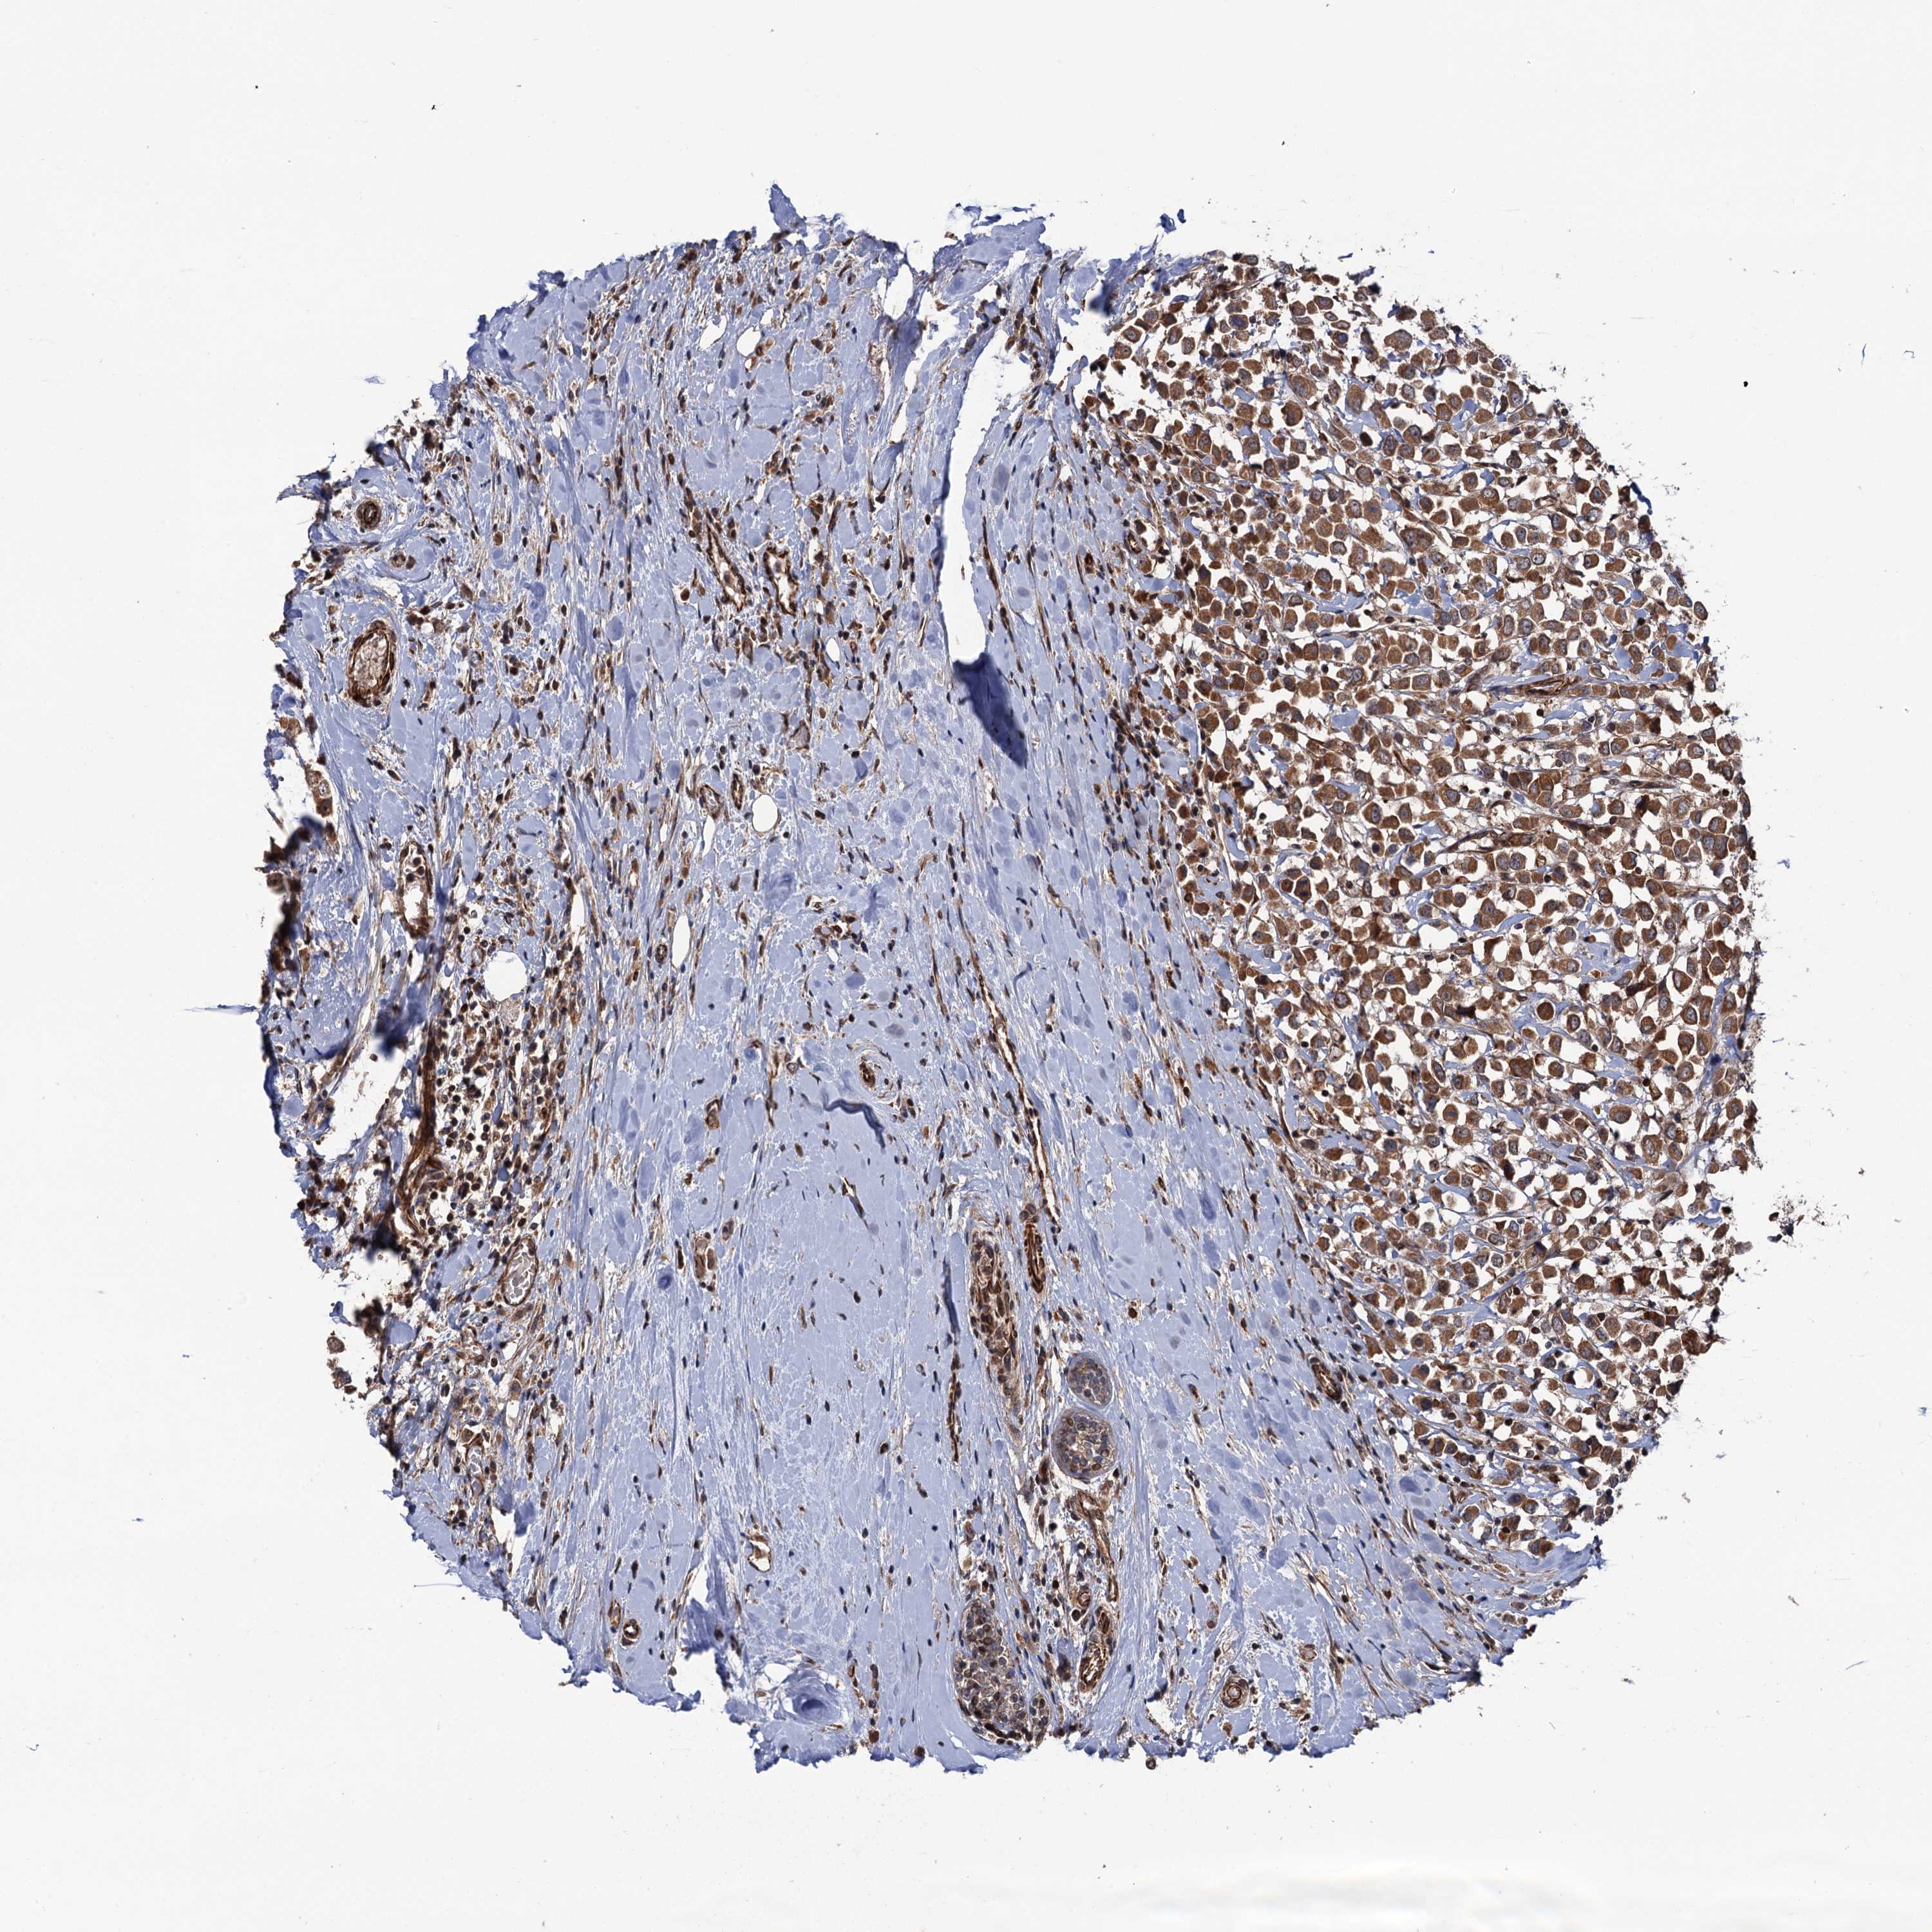

BRCA TCGA BRCA VALIDATION PROTEIN EXPRESSION